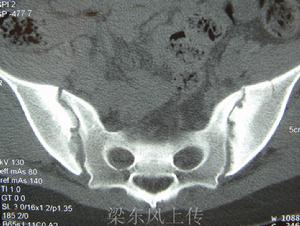

X線表現對強直性脊柱炎具有診斷意義。強直性脊柱炎最早的變化發生在骶髂關節。該處的X線片顯示軟骨下骨緣模糊,骨質糜爛,關節間隙模糊,骨密度增高及關節融合。通常按X線片骶髂關節炎的病變程度分為5級:0級為正常;Ⅰ級可疑;Ⅱ級有輕度骶髂關節炎;Ⅲ級有中度骶髂關節炎;Ⅳ級為關節融合強直。圖1顯示骶髂關節Ⅲ級病變。